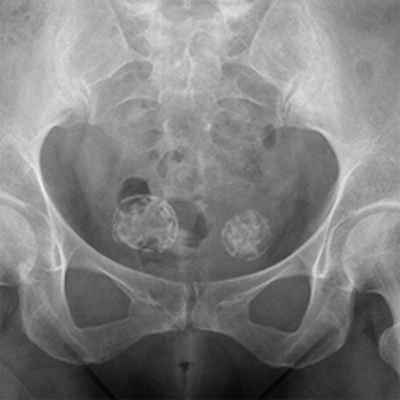

Чаще всего метастатическое поражение костей больше характерно для поражения бедренных и тазовых костей, ребер и позвонков.

Какие кости поражаются при раке

- Кости таза преимущественно ломаются в области лона или вертлужной впадины, как правило, боли невысокой интенсивности, но существенно изменяется походка.